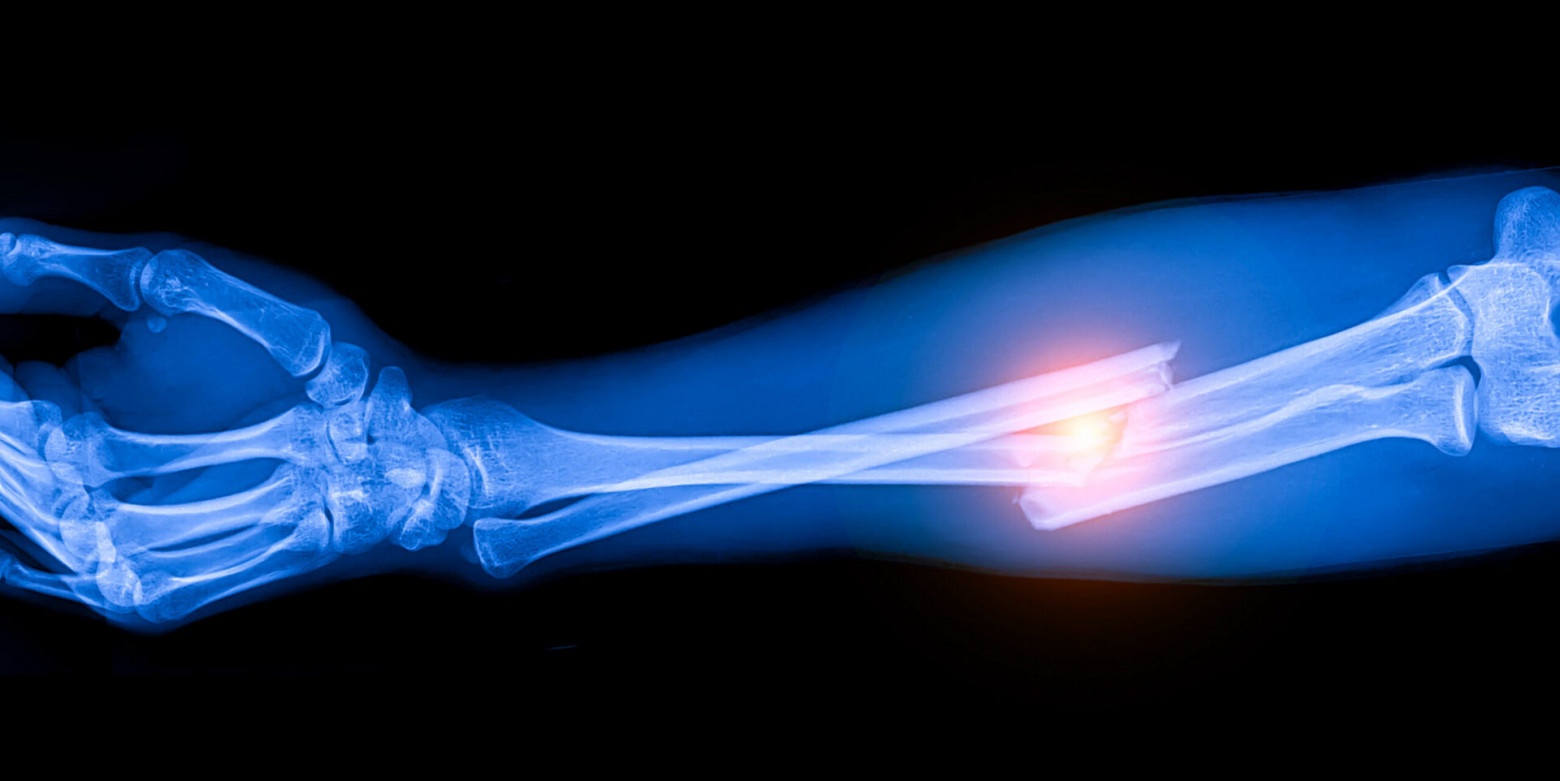

Лечение переломов: 3D-печать гидрогелевого импланта